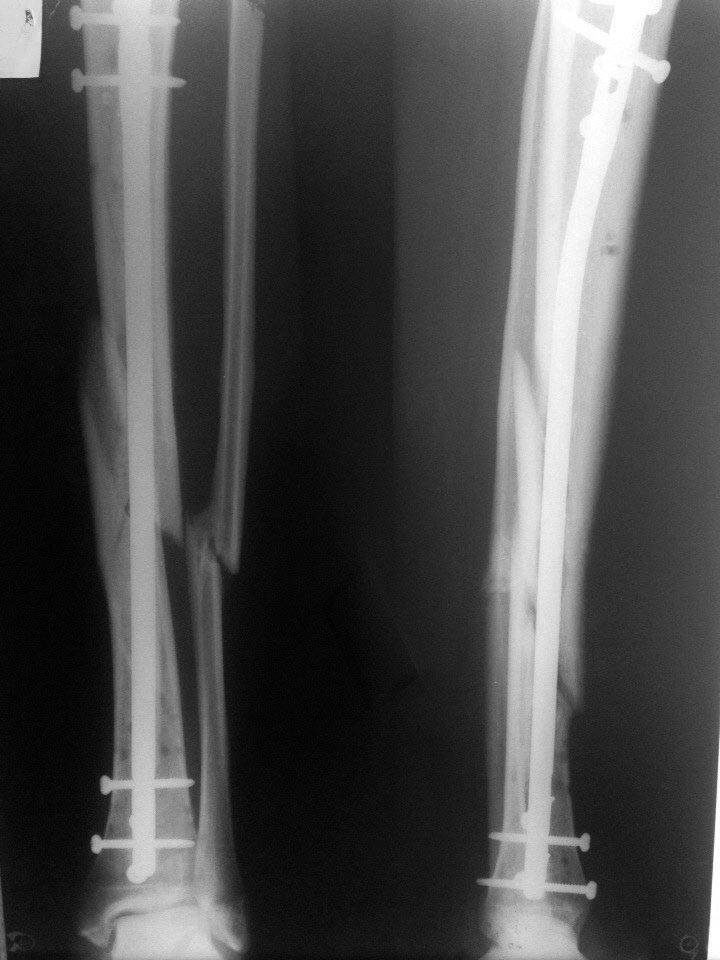

Прошу Вашего совета. Пациент Н. 40 лет прооперирован 11 недель назад.

Закрытая репозиция, БИОС большеберцевой кости с расверливанием. На

повестке дня вопрос о дальнейшей тактике

А. Продолжить ходьбу с нагрузкой в статическом блокировании.

Б. Динамизация с последующей нагрузкой.

В. Третий вариант